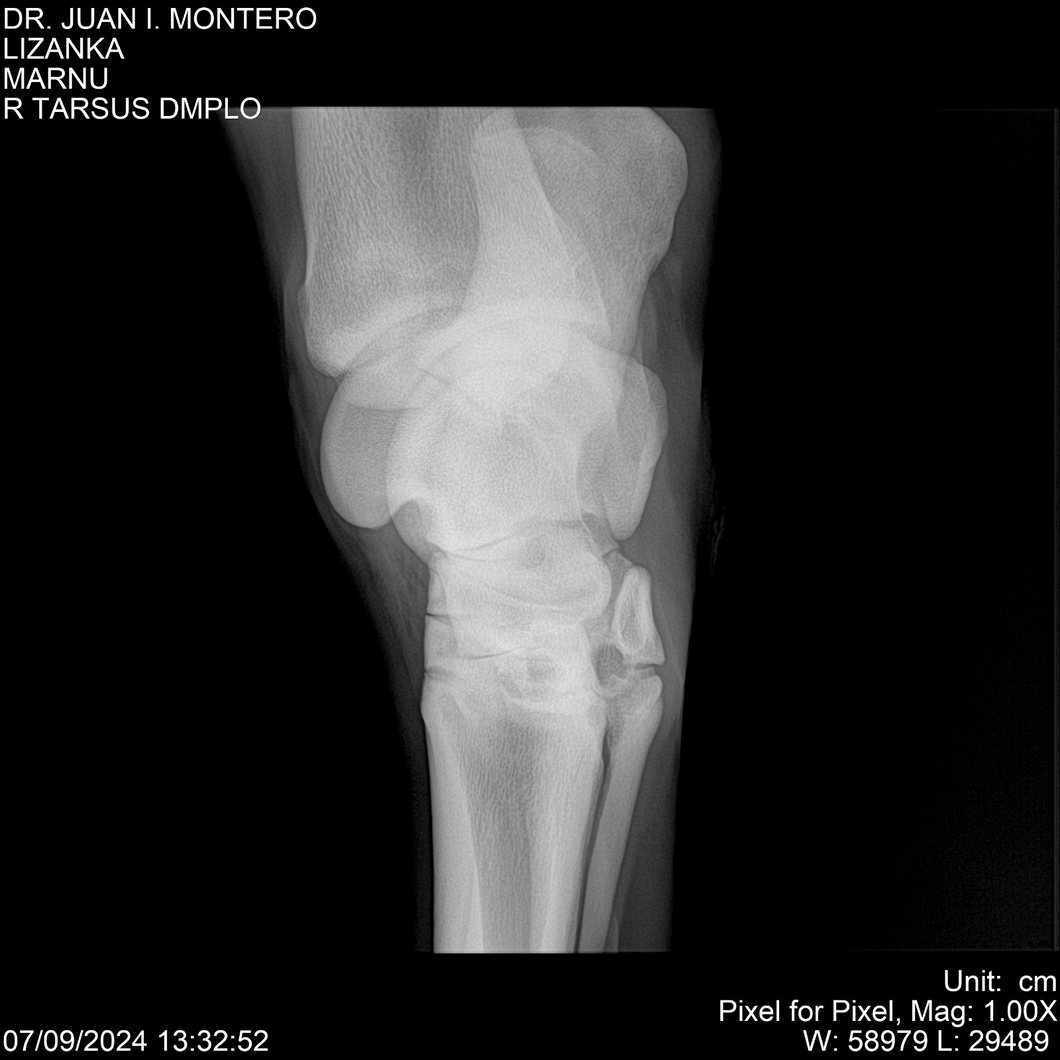

LOTE 18, LIZANKA Lote Anterior Volver al remate Lote Siguiente Ficha Contacto Montevideo - Ficha del Lote Identificador: #282512 Categoría: Yeguarizos Montevideo - 62 Visualizaciones ClicData Contacto Empresa: Abelenda N. R., Walter Hugo Nombre*: Teléfono* : E-mail* : Mensaje Enviar Registrese gratis Este contenido Exclusivo está disponible sólo para usuarios registrados Ingresar